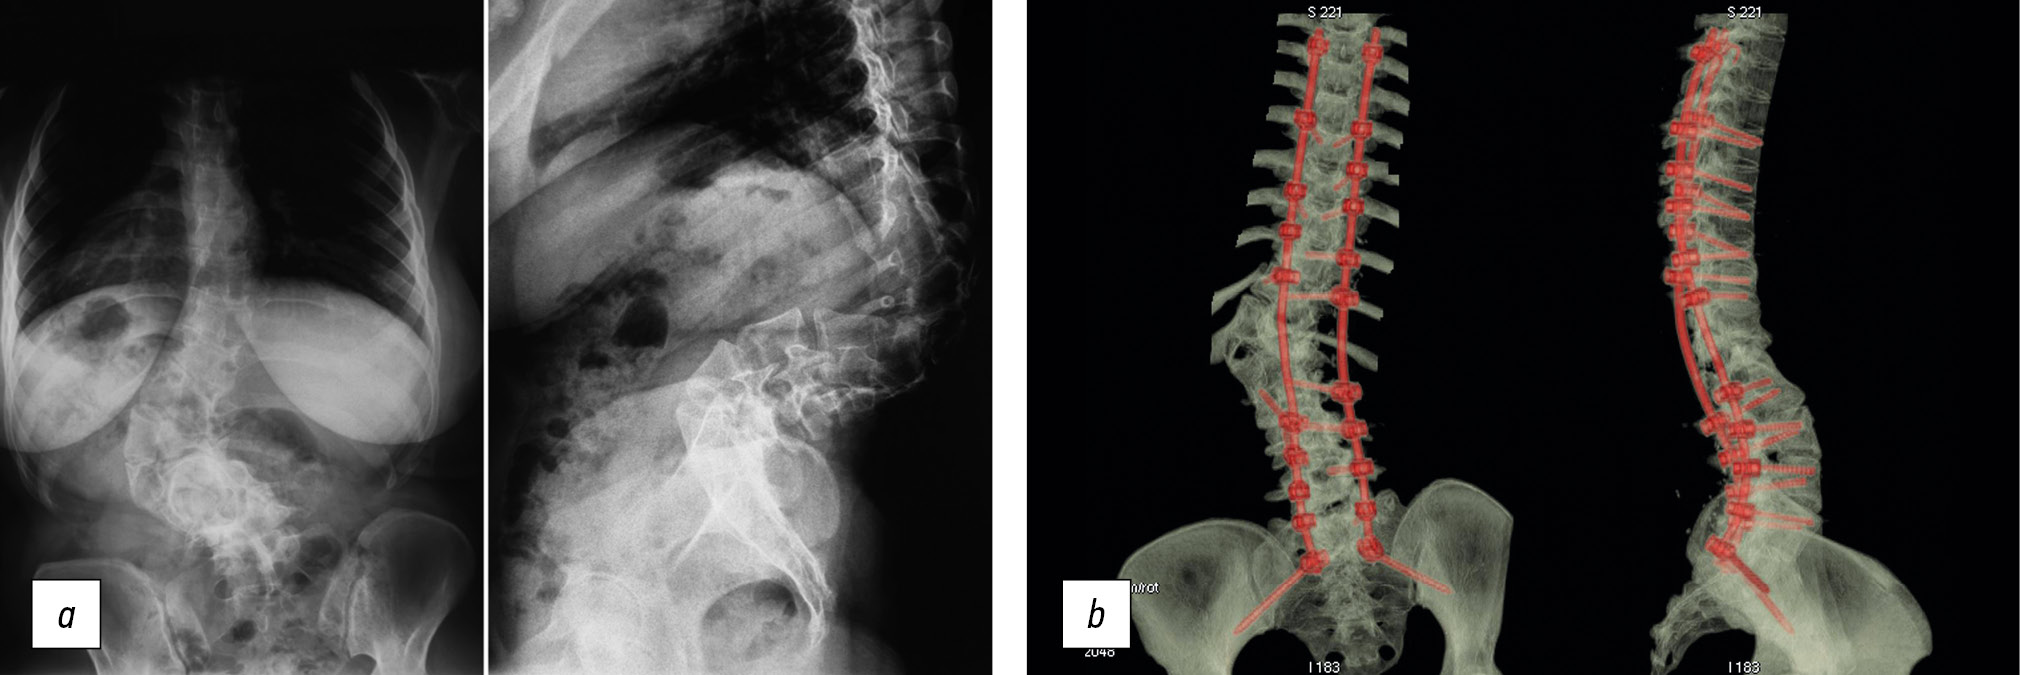

Позвоночно-тазовая фиксация индивидуальными опорными тазовыми пластинами

Восьми пациентам производили позвоночно-тазовую фиксацию индивидуальными опорными тазовыми пластинами. Индивидуальные опорные фиксирующие пластины были спроектированы и выполнены на основании компьютерных и объемных моделей по данным мультиспиральной компьютерной томографии. Все имплантаты были изготовлены на предприятии «Конмет» (Россия), материал — титан Ti-6Al-4V ELI. По стереолитографическим моделям были спроектированы и изготовлены индивидуальные импланты для выполнения позвоночно-тазовой фиксации. Данные импланты имеют форму протяженных пластин, изготовленных таким образом, что внутренние контактные поверхности плотно прилегают к гребню подвздошной кости и части наружной и внутренней поверхностей подвздошной кости. Точное анатомическое соответствие имплантатов и подвздошной кости позволяет осуществить стабильную опорную фиксацию позвоночника посредством соединения стандартно установленной на нем металлоконструкции с опорными тазовыми пластинами (рис. 2).

Рис. 2. Пациент О., 9 лет. Нейрофиброматоз. Деформация пояснично-крестцового отдела позвоночника и таза: а — рентгенограмма и компьютерно-томографическая реконструкция до операции; b — компьютерная модель, проектирование индивидуального импланта; c — стериолитографическая модель с установленной кастомизированной конструкцией; d — рентгенограмма и компьютерно-томографическая реконструкция после выполнения позвоночно-тазовой фиксации индивидуальным имплантатом

Fig. 2. Patient O., 9 years old. Neurofibromatosis. Deformation of the lumbosacral spine and pelvis: a — X-ray and CT reconstruction before surgery; b — computer model, design of an individual implant; c — a sterolithographic model with an installed custom design; d — X-ray and CT-reconstruction after performing spinopelvic fixation with an individual implant